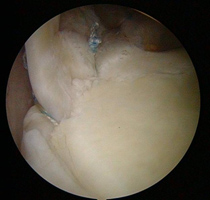

Shoulder Arthroscopic surgery - Superior Labral Anterior to Posterior Tear (SLAP)

This is caused by the biceps tendon comes away from the top of the shoulder socket. First described in 1986 by Andrews in Baseball Pitchers, SLAP is seen more often in the gym with 45-55 year age group pulling weights wrongly. They are also found in keen tennis players. Treatment is given by reattaching the tendon to the (Glenoid) shoulder socket again.

Post - Operation

Pre – Operation